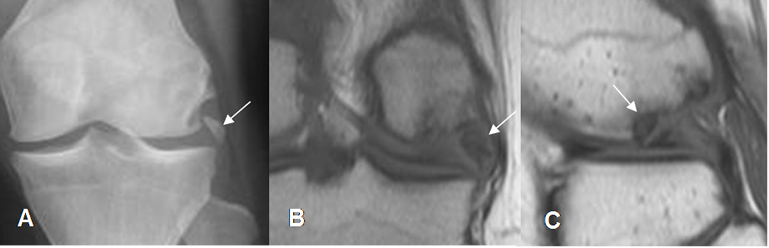

Fig 198. Artropatía degenerativa.

A: Rx AP y B: RM coronal en T1. Cambios degenerativos con formación de osteofitos (Flechas delgadas), disminución de los espacios femorotibiales, erosión de las superficies articulares y lesiones osteocondrales. (Flecha gruesa).